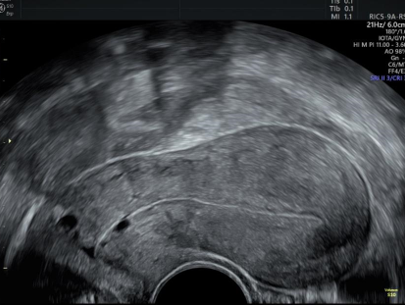

L’échographie gynécologique est un test d’imagerie non invasif (indolore pour les femmes) qui utilise les ultrasons pour visualiser et analyser les organes génitaux internes féminins. Un appareil (transducteur) est utilisé qui émet des sons à haute fréquence imperceptibles à l’oreille humaine, avec lequel des images sont obtenues.

Ce test est très précieux, en raison de la grande quantité d’informations qu’il peut donner. Entre autres choses, il rapporte ce qui suit :

Un examen clinique et une échographie abdomino-pelvienne, permettent de visualiser le contenu de l’utérus : une grossesse intra-utérine arrêtée ou même évacuée et d’affirmer qu’il s’agit d’une fausse couche et non d’une grossesse extra-utérine.

La maladie peut être diagnostiquée via une échographie pelvienne ou endovaginale ou une IRM.